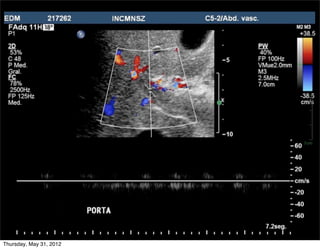

Vena porta

• 70-80% flujo hepático

• Ventanas

• Intercostal oblicua derecha

• Oblicua subxifoidea con angulación craneal

Porta normal

• Abordaje: variable, en general

intercostal

LAMINAR: petal y ligeramente ondulante

• Flujo normal (petal)

• Hacia el transductor (rojo)

15-40 cm/seg

Porta común